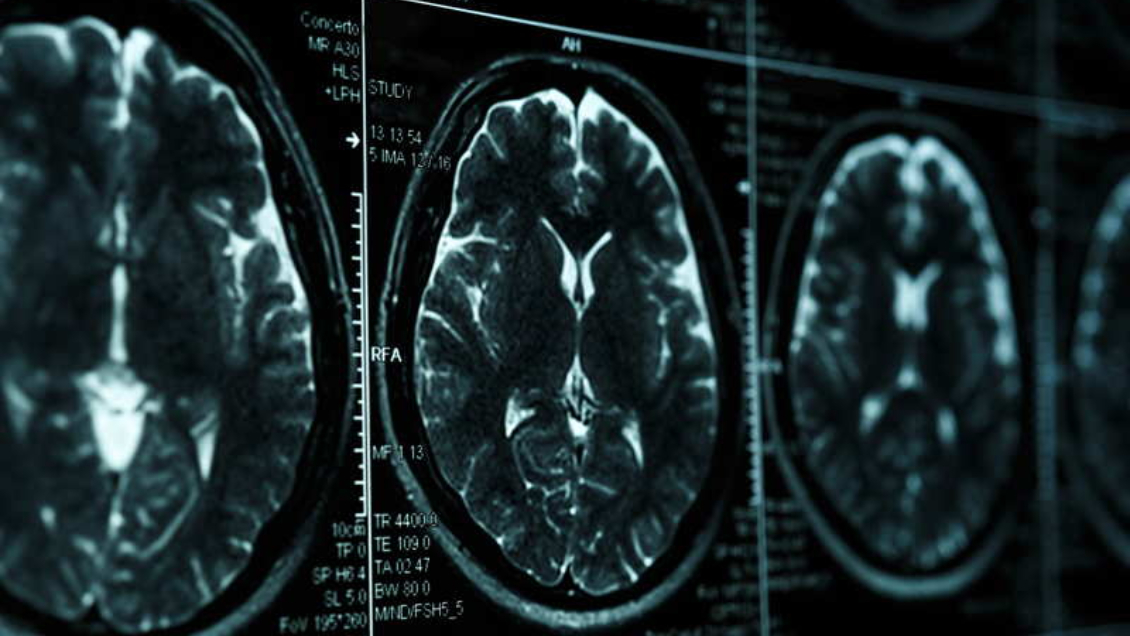

El fármaco, que se administra por vía intravenosa, ha despertado suspicacias por la posibilidad de que provoque inflamación y sangrado en el cerebro, una condición que se da en algunos pacientes de alzhéimer, conocida como ARIA.

La FDA admitió en su comunicado que Leqembi puede generar efectos secundarios como dolor de cabeza o incluso ARIA, que generalmente se resuelven con el paso del tiempo pero que en casos raros pueden resultar mortales.